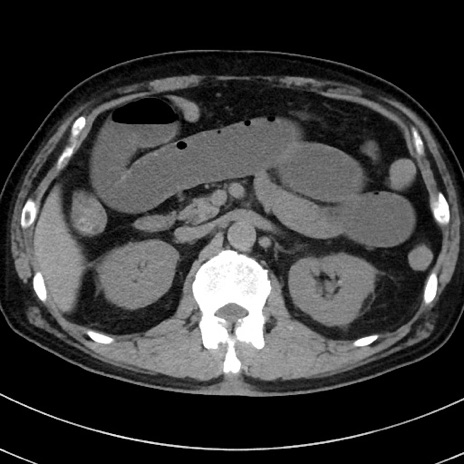

症例38(横断像)

【症例】70歳代 男性

【主訴】腹痛・嘔吐

【現病歴】昨晩より、嘔吐・腹痛あり。今朝になっても嘔吐あり。来院。

【既往歴】心臓バイパス手術、開腹胆摘、腸閉塞

【身体所見】BP 107/71mmHg、HR 116/min、腹部:平坦、軟、下腹部に軽度圧痛あり。反跳痛なし。

【データ】WBC 15100、CRP 0.32